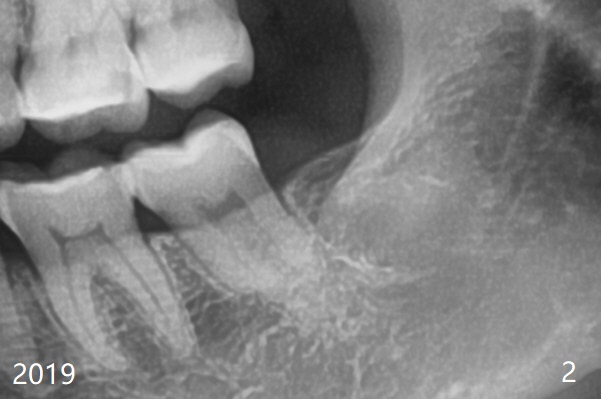

术后2.5月第二,三磨牙之间牙槽嵴薄(图二:>),术中破坏少